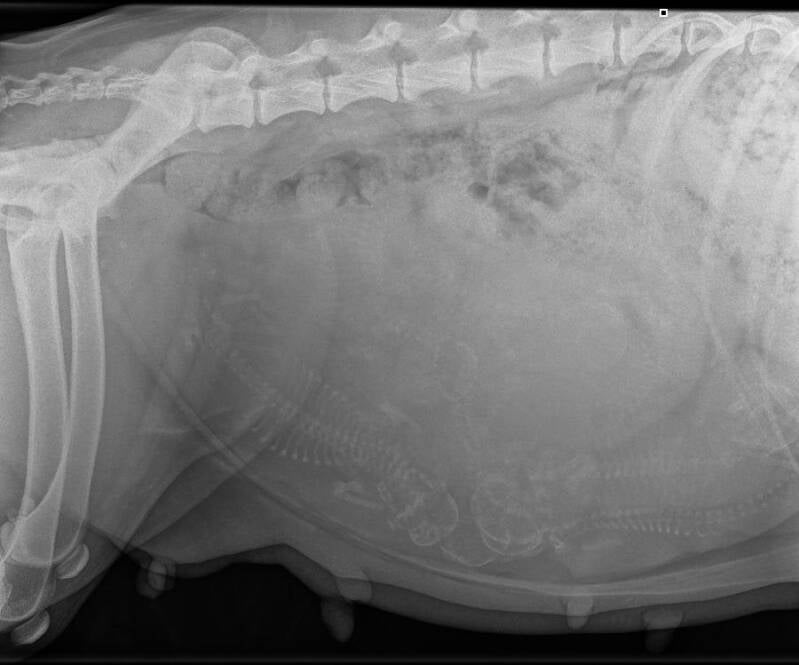

We zijn vandaag naar de dierenarts geweest om een röntgenfoto te maken.  Er was wat tussen gekomen op vrijdag waardoor we de afspraak moesten verzetten naar woensdag.

Xanthy vond het leuk bij de dierenarts, want ze kreeg lekker veel aandacht. Ik heb geholpen bij het maken van de röntgenfoto. Hiervoor moest ik natuurlijk beschermende kleding aan. Daarna heb ik bij haar kop gestaan om te zorgen dat ze rustig bleef liggen.

Ze deed het fantastisch. Ze was wel veel aan het hijgen.

Op deze foto is het best moeilijk te zien, maar bij de dierenarts konden we het wel goed te zien. De dierenarts telde er 9 pups. Dat had ik niet verwacht. Ik ging een beetje uit van 6 puppy's, maar was blij verrast.

Ze heeft ook een enorme buik. En is het niet verwonderlijk dat ze het lopen niet zo prettig vind. Ze is best veel aangekomen in gewicht, maar ze is absoluut niet te dik. Ze mag al best wel weer meer brokken krijgen.